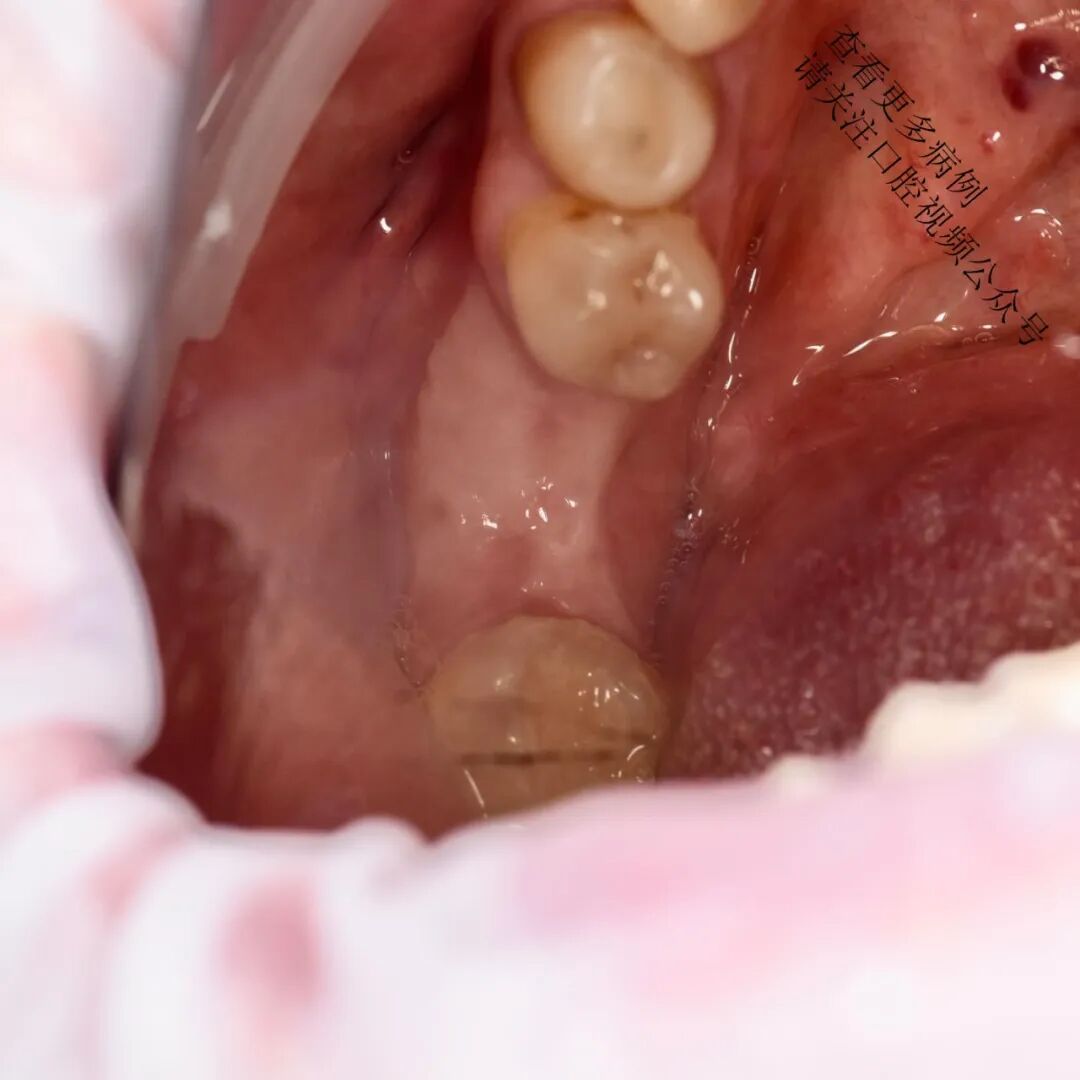

翻制半厚瓣,去除肌肉纤维牵拉

将可移动黏膜固定至根方骨膜(使用6/0单丝缝线,如Monocryl)

从腭部获取结缔组织移植材料(CTG / ССТ)

使用不可吸收缝线(如Prolene 6/0)将移植片紧密固定于骨膜上